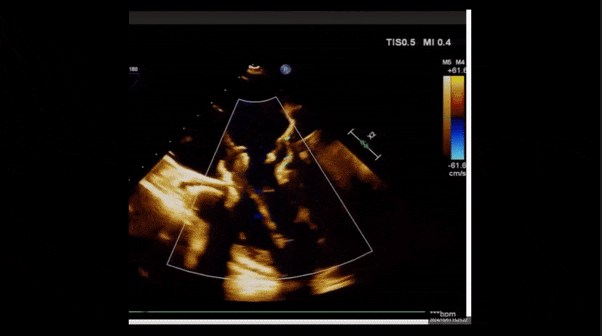

1、3D TEE顯示雙房及右室擴大,右室中段直徑40mm,右室FCA 52%。三尖瓣環(huán)TAPSE 22mm,三尖瓣環(huán)左右徑49mm,三尖瓣隔葉長度16mm,前葉長度21mm,后葉長度34mm,三尖瓣前隔gap 11mm,后隔gap 5.6mm,AP gap 12mm,診斷極重度功能性三尖瓣返流(Type I型三尖瓣:Torrential FTR 5+)。

2、彩色多普勒顯示:收縮期三尖瓣口返流束起源于后隔交界、前后葉之間及前隔交界,返流束縮流頸最大寬度27mm,三尖瓣返流口EOA=2.02cm2,返流容積124ml,收縮期三尖瓣返流峰值速度2.64m/s,返流峰值壓差28mmHg,PAPs 43mmHg,舒張期三尖瓣口平均跨瓣壓差1mmHg,肝左靜脈可見明顯逆向血流波。